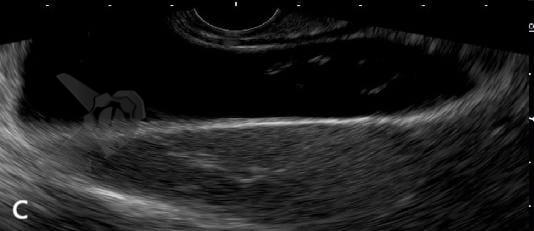

A poeira biliar foi definida como imagem flutuante hiperecogênica, sem sombra acústica posterior, observada ou acentuada após palpação abdominal³. Trata-se, portanto, da mesma entidade ecográfica que, no Brasil, vinha sendo tradicionalmente denominada “microlitíase”, mas que não se enquadra na definição do consenso internacional de microlitíase e acabou sendo praticamente ignorada pelo consenso — ou, em alguns casos, forçadamente incluída sob o amplo guarda-chuva do termo “barro biliar”.

A poeira biliar (“biliary dust”) foi definida como imagem flutuante hiperecogênica, sem sombra acústica posterior, observada ou acentuada após palpação abdominal — entidade ecográfica previamente denominada “microlitíase” ou “microcálculo” em nosso meio. A introdução desse termo visa conciliar os achados ecográficos frequentemente observados na prática diária com as definições estabelecidas pelo Consenso Internacional de 2023.